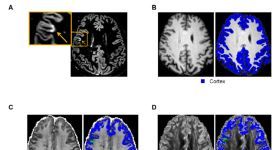

目的:應(yīng)用神經(jīng)軸突定向彌散和密度成像(NODDI)探究多發(fā)性硬化癥(MS)患者正常皮質(zhì)(NA,normal- appearing (NA) c...